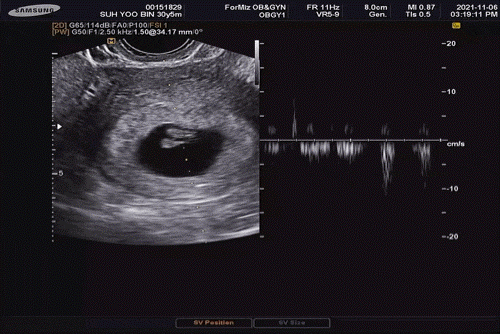

4주 6일 병원에 가서 아카짱의 집을 확인!10주까지는 질 초음파로 봐 주실 예정.심장 소리를 들을 때 모자수첩을 받기로 했고, 산전검사 결과 갑상선 수치가 경계선에 있어서 갑상선 수치 검사도 그때 같이 하기로 했다!

7주 1일 심음 확인

7주 6일 심장 소리 확인!뿅뿅 뛰는 거 진짜 귀여워남편의 대학원 시간때문에 토요일 오후에 진료받는 병원에 갔었는데…후회했다.다음부터 다시 목동제일여성병원에 갈 예정^^